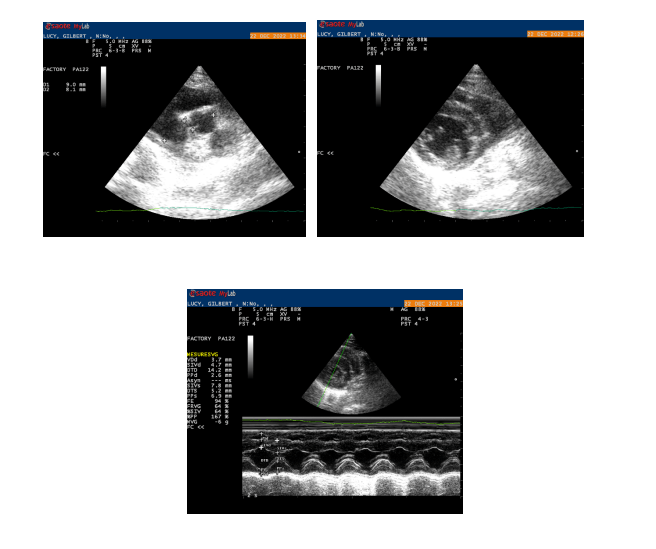

Le Dr Gillier est formée pour effectuer des échocardiographies pour diagnostiquer des maladies cardiaques.

Cette examen complémentaire est conseillé après une suspicion de pathologie cardiaque relevée pendant la consultation, comme un souffle cardiaque, de la fatigue à l’effort ou, dans les cas plus graves, lors de décompensation cardiaque.